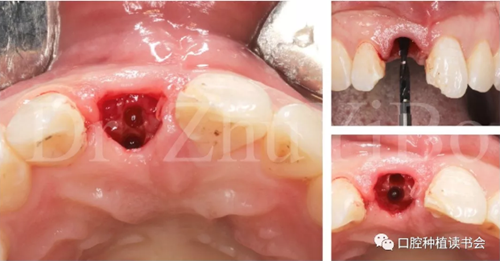

一位年輕女性患者,右上中切牙外傷冠根折2日。

臨床檢查發(fā)現(xiàn):右上中切牙冠根折,斷面位于齦緣下4到5個毫米。左上中切牙及右上側切牙,切角缺損,牙髓活力正常(圖7)。

圖7 外傷導致11冠根折

4.2.1微創(chuàng)拔出牙齒,挺出根尖(圖9)

圖9 斷裂牙根需用微創(chuàng)器械拔除

4.2.2 拔牙窩沖洗,定點,備洞(圖10)。

圖10 種植窩洞相對于天然牙長軸偏向腭側